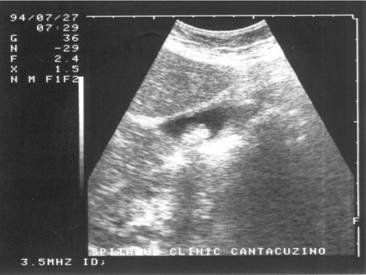

Figura 18. Con de umbra in litiaza renala

Figura 19. Con de umbra posterioara in litiaza biliara